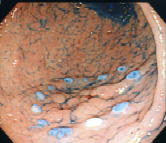

早期胃がんのESD症例

早期のがんを内視鏡と特殊なナイフを使用して切り取る方法をご紹介します。

2. 切除範囲確定のためのマーキング |